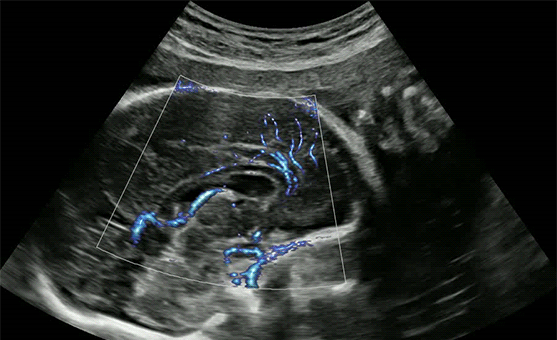

Le innovative tecnologie proprietarie di Samsung supportano la diagnosi assicurando un maggiore dettaglio e velocizzano i flussi di lavoro.